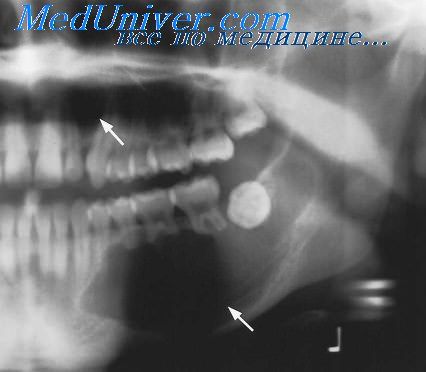

Рентгеновские снимки посттравматического остеомиелита челюсти: Медицинские случаи

Раздел: Образы вокруг